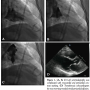

A 69-year-old male presented with inferior wall ischemia. Transradial coronary angiogram with an Optitorque catheter with Jacky shape tip (Terumo Medical Corporation) showed unobstructed coronary arteries. Left ventriculography was complicated with myocardial and pericardial contrast staining (Figures 1A, 1B, and 1C; video available at www.invasivecardiology.com). The catheter was pulled back. The patient experienced sharp chest pain that resolved in 20 minutes. Stat transthoracic echocardiogram was unremarkable. The patient remained hemodynamically stable. Transthoracic echocardiogram the next morning revealed trivial pericardial effusion (Figure 1D). The patient was asymptomatic on outpatient follow-up. The Optitorque transradial catheter with Jacky and Tiger shape tips is the preferred multipurpose catheter for transradial coronary angiogram. Potential complications of ventriculogram catheters are myocardial staining, myocardial rupture, cardiac tamponade, and arrhythmias caused by improper catheter tip position. It is imperative to check the proper position of the catheter tip prior to left ventriculography (even though we checked our position with a small test injection) to avoid these types of complication. The operator should carefully look at the waveform from the transducer to ensure that catheter tip is in the mid left ventricle rather than base and also confirm with hand-held test injection in right and left anterior oblique views that the catheter tip is not against the wall. This case illustrates the value of careful manipulation and placement of transradial catheter during left ventriculography.